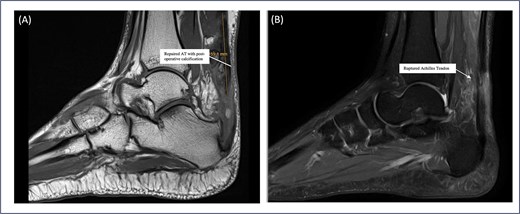

Patient 5 is a 46-year-old female. The patient sustained an ankle twisting injury leading to acute ATR. She has a pre-existing Haglund deformity (Fig. 3A) and developed postoperative calcification near the tendon insertion, which is 6 mm in length. However, no functional limitations or discomfort during dorsiflexion were felt clinically (Fig. 4); this might be a mild complication secondary to local irritation of the tendon or altered healing due to the presence of a bony prominence. She underwent right Achilles tendon repair with flexor hallucis longus (FHL) transport and Y lengthening. She began weight-bearing at 3 weeks following the same protocol as other patients. However, at the final follow up the patient had not yet returned to sports and reported an ATRS score of 75, the lowest amongst the patients in the series. This indicates that there are ongoing limitations in function or confidence. Whilst the patient’s surgical and post-operative course was uneventful, this may reflect delayed tendon remodelling, reduced strength, pain or psychosocial factors such as fear of re-injury.

Sagittal MRI sequences of Patient 5 showing calcific changes and tendon status. (A) MRI highlights a 6 mm postoperative calcification near the Achilles tendon insertion site. (B) MRI confirms intact Achilles tendon continuity with no evidence of re-tear.